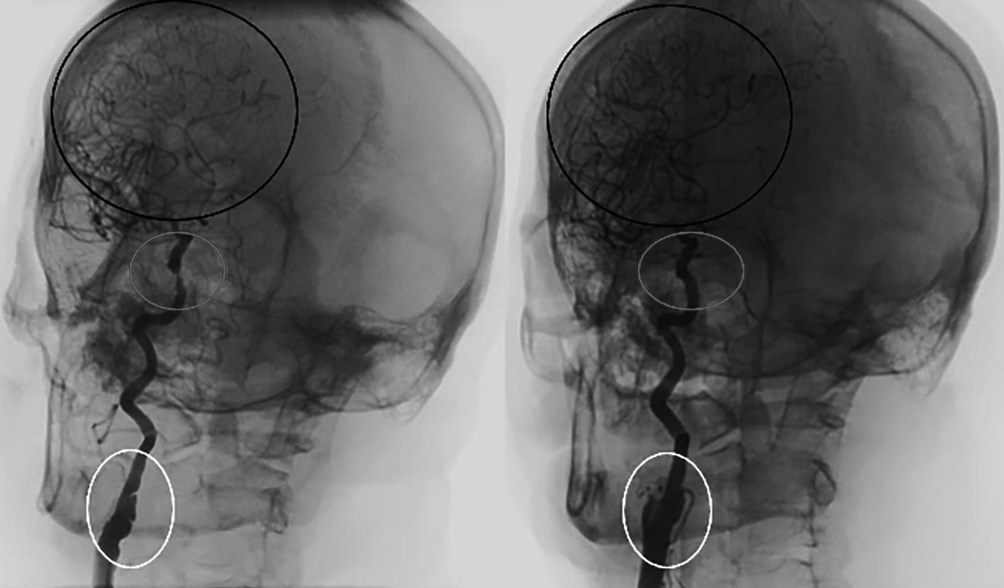

По данным мультиспиральной компьютерной томографии (МСКТ) головного мозга выявлены постишемические кисты теменной доли правой гемисферы (рис. 1). Признаков ОНМК не установлено, шкала ASPECTS (Alberta Stroke Program Early CT Score) — 10 баллов [17].

Рис. 1. Бесконтрастная КТ головного мозга пациента М. при поступлении. ASPECTS 10 баллов. / Fig. 1. Plain brain multislice computed tomography of patient M. on admission. ASPECTS 10.

Учитывая сохранение кровотока на уровне TICI3 по правым ВСА и средней мозговой артерии, а также повышенный риск геморрагической трансформации на фоне назначения антиагрегантной терапии и гепаринизации от экстренного стентирования решено отказаться в пользу первичной консервативной тактики. Через 24 ч после повторной МСКТ (рис. 4) рекомендовано начать двойную антиагрегантную терапию. Спустя 12 ч после госпитализации у пациента отмечен полный регресс симптоматики.

Рис. 4. МСКТ пациента М. через 24 ч после поступления. ASPECTS 10 баллов, данных за геморрагическую трансформацию не получено. / Fig. 4. Patient M.'s MSCT scan in 24 h after admission. ASPECTS 10, no signs of hemorrhagic transformation.